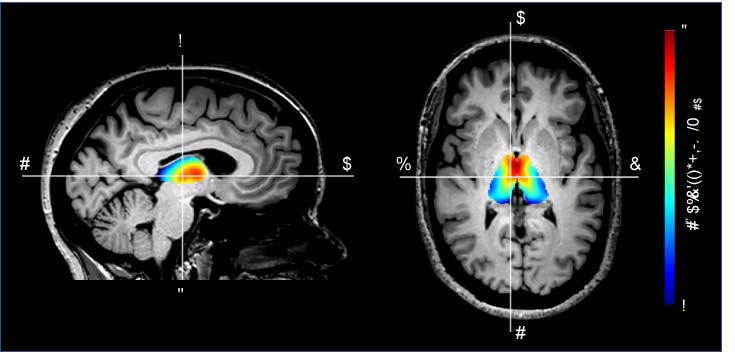

The Darby lab investigates the neural mechanisms underlying the most complex human behaviors at the interface of neurology, psychiatry, and philosophy, including moral behavior, delusions, and free will perception. Our lab’s overarching hypothesis is that these behaviors will not localize to a single brain region, but rather to common networks of connected brain regions that work together to bring about complex human behaviors. Our lab has worked to develop novel neuroimaging methods to test this network localization hypothesis in patients with focal brain lesions, dementia, and even psychiatric diseases. We also explore the ethical and legal implications of our research.